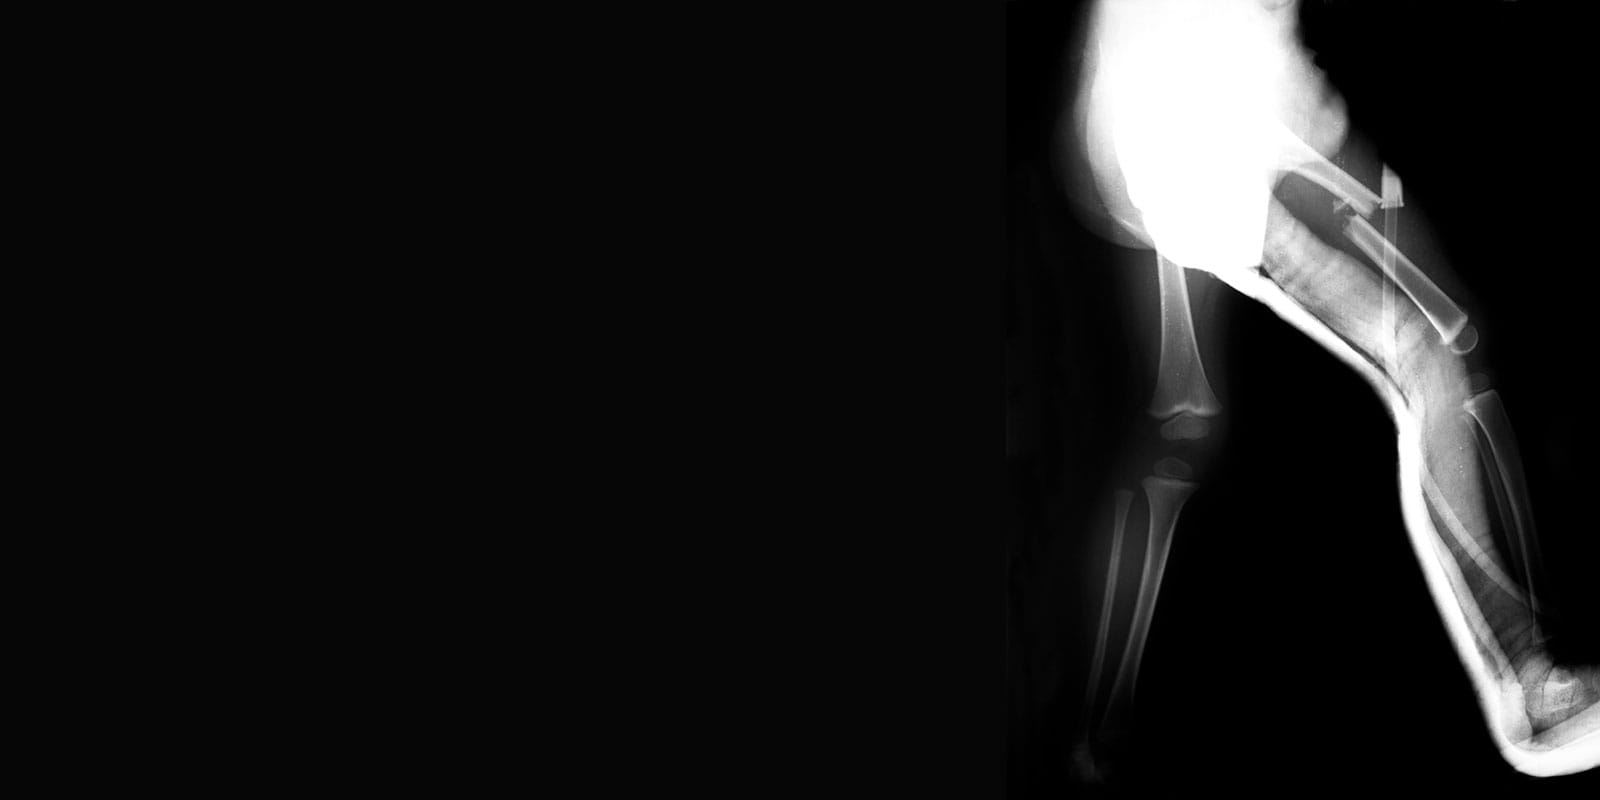

Our expert pediatric orthopedics team in University Hospitals Rainbow Babies & Children’s Hospital fracture and trauma program treats pediatric musculoskeletal injuries, which can present special challenges that affect growth and development. Our specialists treat all types of fractures and sports injuries, as well as life-threatening traumatic injuries, such as serious spinal trauma and polytrauma, or injuries to multiple parts of the body.

Trauma expertise: As part of Cleveland’s only Level I pediatric trauma center, our fracture and trauma team treats the full spectrum of orthopedic fractures and injuries, from minor sports injuries to complex traumatic injuries that involve multiple fractures.

Growth plate care: Our pediatric fracture and trauma care have special expertise in treating injuries to avoid damage to growth plates, which can prevent potential growth problems and/or deformities as a child continues to grow.

With growth-plate injuries, pediatric orthopedic surgeons are expertly trained to treat the fracture or trauma to prevent permanent growth issues or possible deformity. Growth plates are the growing tissue at both ends of long bones in children and adolescents, which determine the length and shape of the mature bone. The orthopedic physicians at UH Rainbow Babies & Children’s Hospital often work closely with other pediatric specialists, depending on the type of case they are treating. Our doctors also coordinate with occupational and physical therapists, who play an essential role in helping young children regain their function and mobility after injuries to ensure a strong recovery for continued growth.